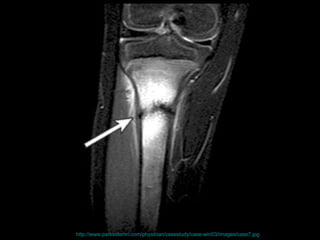

http://www.parksidemri.com/physician/casestudy/case-win03/images/case7.jpg

http://www.parksidemri.com/physician/casestudy/case-win03/fig6.html